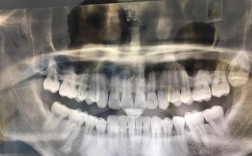

上海宏康牙齿矫正的核心优势在于“精准诊断+个性化方案+全程数字化管理”,初诊时,医生会通过口内扫描、CBCT影像拍摄、头影测量等多项检查,获取牙齿、颌骨、面型的三维数据,利用数字化正畸系统模拟牙齿移动路径,预测矫正后的效果,让患者在治疗前即可“预见”变化,专家团队会结合模拟结果与患者沟通,制定包含拔牙与否、矫正周期、费用明细的个性化方案,避免“千人一方”的流水线操作,矫正过程中,科室引入智能正畸监测系统,可实时追踪牙齿移动进度,动态调整施力方案,有效缩短矫正周期(较传统方式平均缩短3-6个月),同时降低不适感。